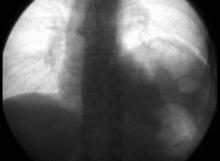

The phrenic nerve descends obliquely with the internal jugular vein across the anterior scalene, deep to the prevertebral layer of deep cervical fascia and the transverse cervical and suprascapular arteries. On the left, the phrenic nerve crosses anterior to the first part of the subclavian artery. On the right, it lies on the anterior scalene muscle and crosses anterior to the 2nd part of the subclavian artery. On both sides, the phrenic nerve runs posterior to the subclavian vein as it enters the thorax where it runs anterior to the root of the lung and between the fibrous pericardium and mediastinal face of the parietal pleura.[1]

Found in the middle mediastinum, both phrenic nerves run from C3, C4, and C5 along the anterior scalene muscle deep to the carotid sheath.

- The right phrenic nerve passes over the brachiocephalic artery, posterior to the subclavian vein, and then crosses the root of the right lung anteriorly and then leaves the thorax by passing through the vena cava hiatus opening in the diaphragm at the level of T8. The right phrenic nerve passes over the right atrium.

- The left phrenic nerve passes over the pericardium of the left ventricle and pierces the diaphragm separately.